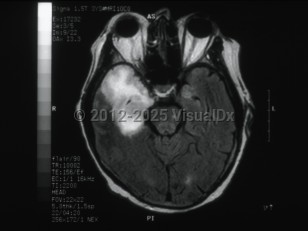

Herpes simplex virus encephalitis

Herpes simplex virus encephalitis, typically caused by herpes simplex virus type 1 (HSV-1), is characterized by the acute onset of fevers, headaches, and other neurologic signs and symptoms, including seizures, altered levels of consciousness, and personality changes. HSV encephalitis is the most common cause of sporadic fatal encephalitis in the United States and worldwide. Even with antiviral therapy, HSV encephalitis can result in significant morbidity and can even be fatal.

Clinically, patients typically present with focal neurologic signs that have been present for <1 week.  In most cases of HSV encephalitis, the temporal lobe of the brain, usually unilateral, undergoes necrosis, and clinical findings reflect the areas of the brain that are affected. They include altered levels of consciousness, behavioral changes, focal cranial nerve deficits, ataxia, aphasia, and seizures. The majority of patients will also present with fever. The behavioral changes most commonly associated with HSV encephalitis are hypomania (including elevated mood, excessive animation, hypersexuality, and decreased sleep requirements), amnesia, and Klüver-Bucy syndrome, which is a behavioral syndrome that involves loss of typical anger and fear responses and increased sexuality. The Klüver-Bucy syndrome is thought to be associated with the proclivity of HSV encephalitis for the temporal lobes and limbic system structures. More rarely, HSV encephalitis can present as a brainstem syndrome and can result in the syndrome of inappropriate antidiuretic hormone secretion (SIADH).